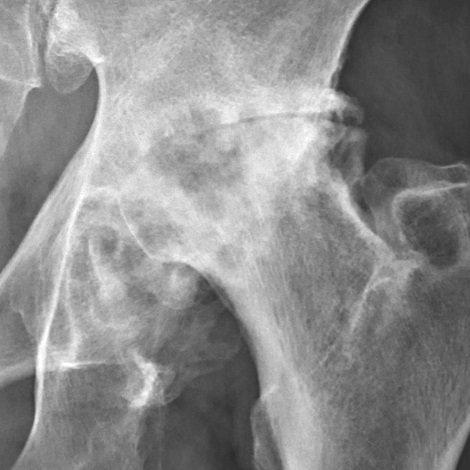

Анатомическая иллюстрация коксартроза — изменения в тазобедренном суставе при артрозе Источник: Wikimedia Commons / CFCF, CC BY-SA 4.0

По словам автора, коксартроз третьей степени — когда суставная щель почти не просматривается, хрящ разрушен, на костях видны остеофиты и кисты — в классической медицине считается стопроцентным показанием к эндопротезированию. Но клиническая практика и специальные исследования, по его словам, доказали: даже в таких случаях операцию часто можно отменить или отсрочить на многие годы. Анатомическое разрушение сустава на рентгене не всегда ставит крест на его функции. Если снять перегрузку и восстановить кровоток — тело запускает собственный, прежде заблокированный процесс регенерации.